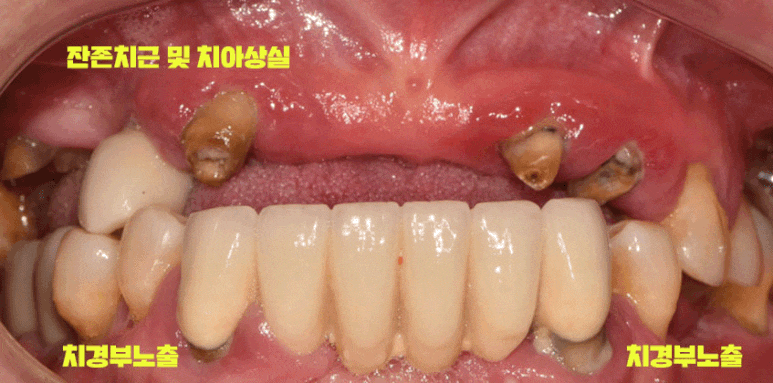

앞니 상실 및 잔존 치근

구강위생 불량 (다수의 치석, 충치, 잇몸 염증)

정출

치경부 드러남

크게 4가지를 꼽을 수 있겠군요.

엑스레이를 보면 남아있던 치아 대부분에서 치근단 염증(뿌리)이 진행되고 있었는데요.

조금만 내버려 둬도 곧 자연 발치가 될 것으로 예상되었습니다.